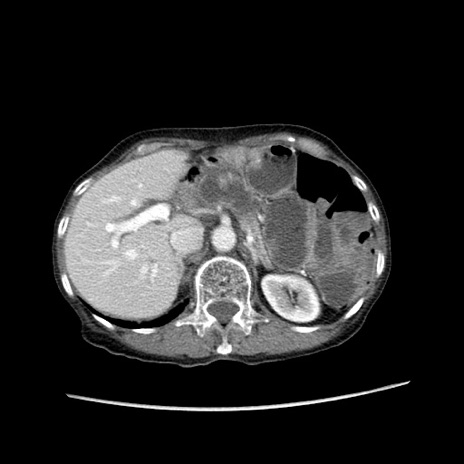

症例25(横断像)

【症例】80歳代女性

【主訴】胸のつかえ感

【現病歴】約9時間前に食後から胸のつかえた感じあり、嘔吐あり、来院。

【既往歴】胃癌(全摘)、胆摘、虫垂炎

【身体所見】心窩部に圧痛あり、反跳痛なし。

【データ】WBC 5700、CRP 0.05